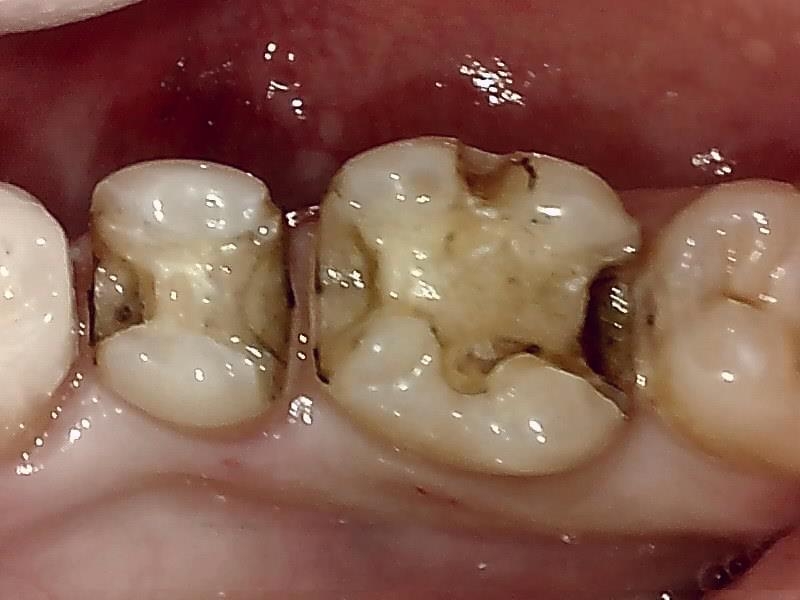

7近心隣接面の齲窩の写真